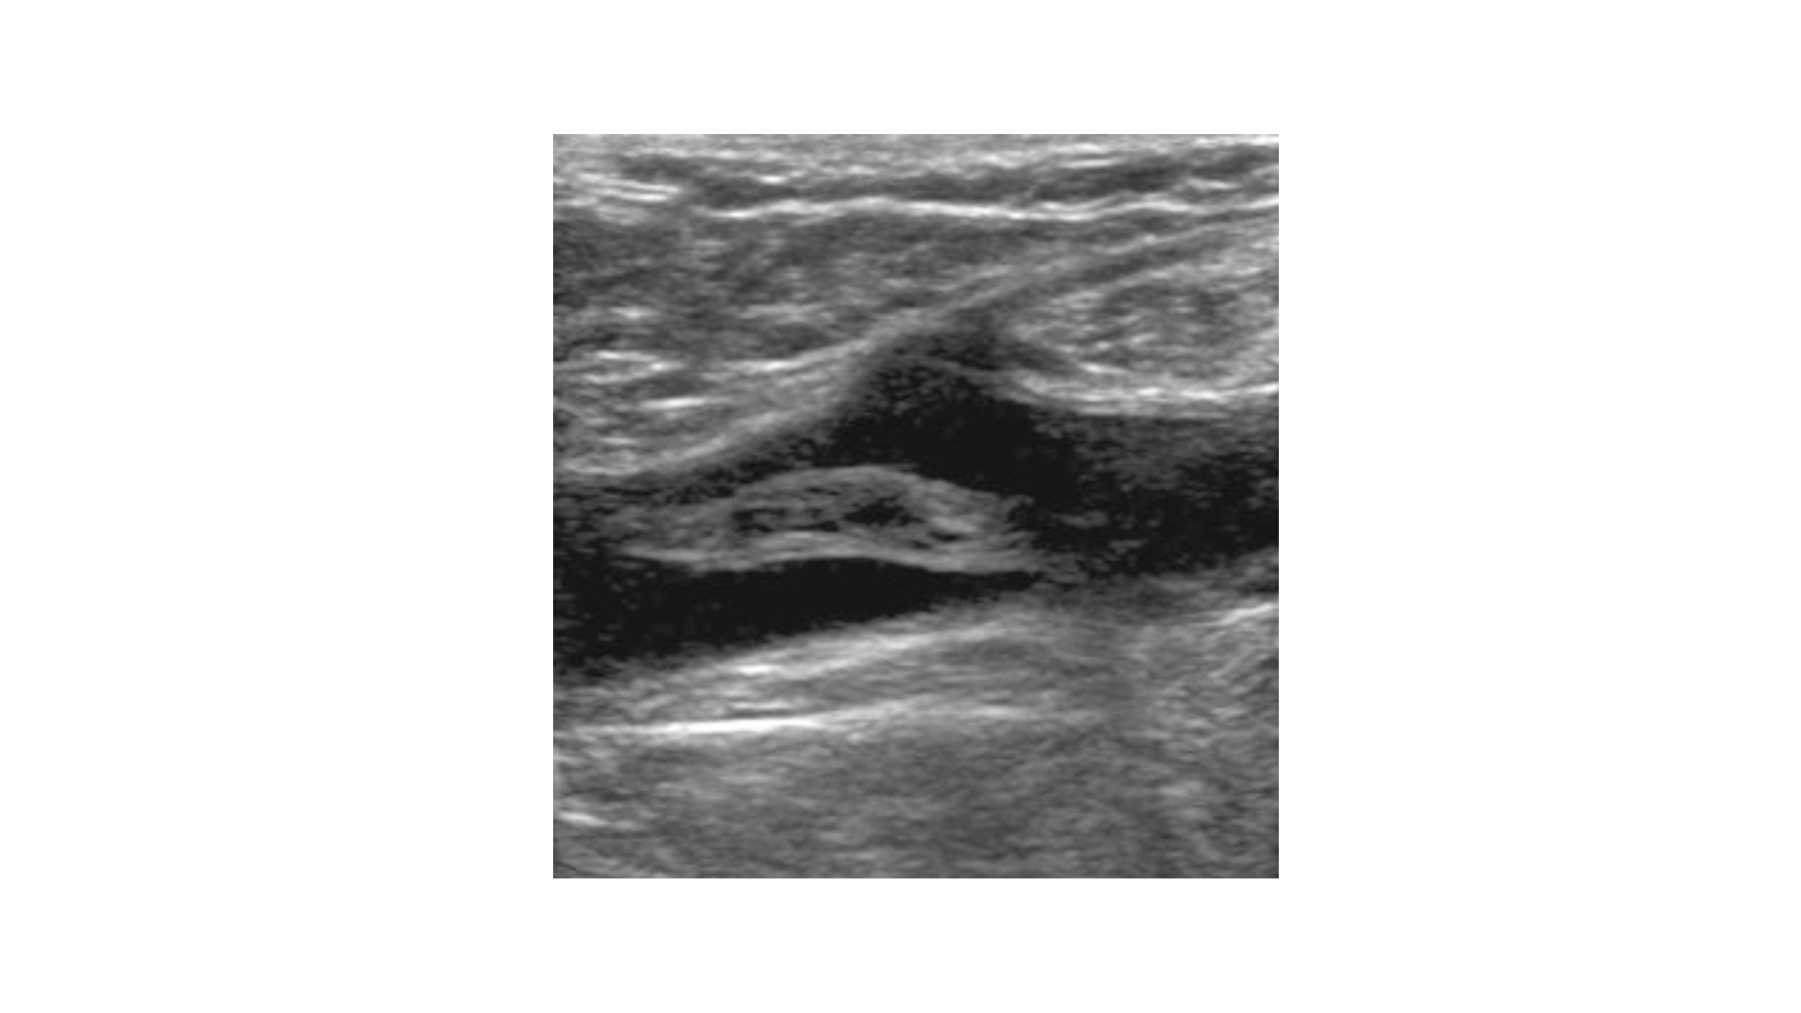

سۆنهری دوپلێکس